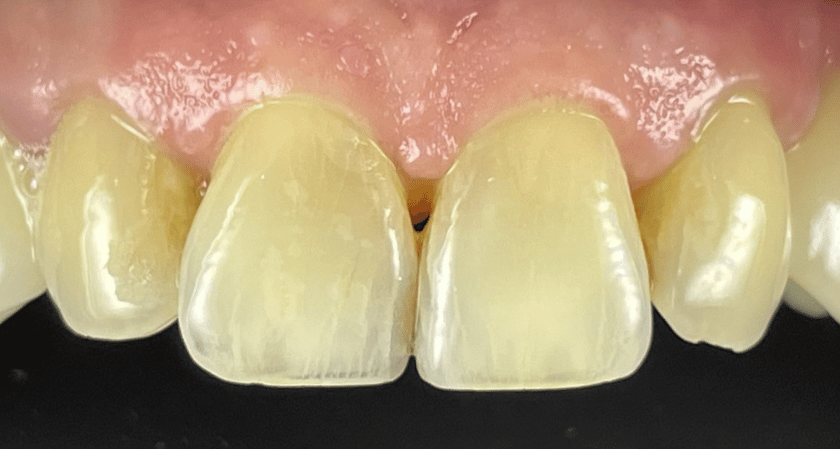

LEARN MORECase 22

This patient had a combination of implants for her missing teeth and crowns for the existing teeth.